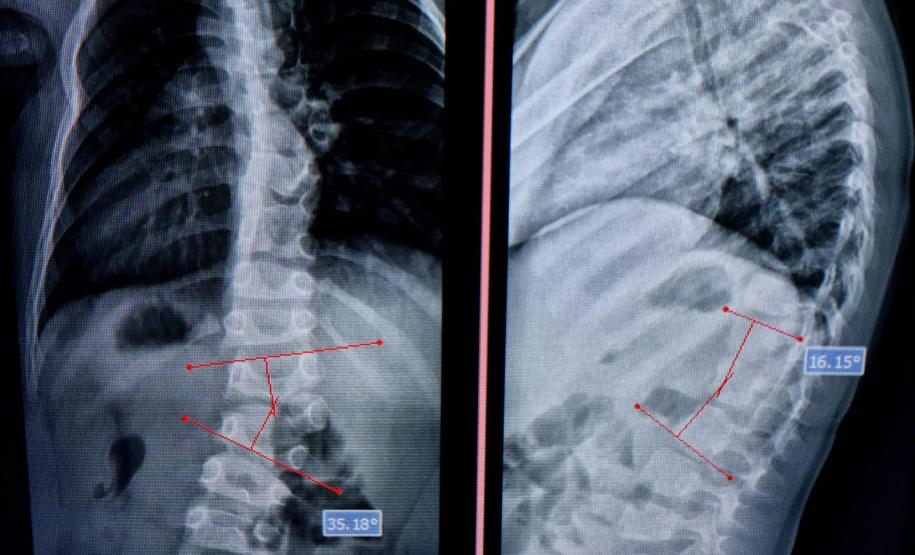

Aos 14 anos, a adolescente Milena de Andrade Carvalho, moradora de Guaratuba, no Litoral do Estado, foi diagnosticada com escoliose idiopática. Sem causa definida, esse tipo de escoliose pode surgir a partir dos quatro anos até a adolescência e ocorre durante o estirão de crescimento. Quando a condição da curvatura ultrapassa os 40 graus, a escoliose se torna progressiva e o paciente continua entortando. Essa condição ocorre com maior frequência em meninas e é muito importante que os pais estejam atentos a qualquer sinal do problema.

“Descobrimos a escoliose por acaso, nunca tínhamos percebido a deformidade, até que um dia ao amarrar meu biquíni, minha mãe observou que eu estava com a coluna torta e ao passar a mão percebeu a curvatura. Decidimos então procurar atendimento médico e tive o diagnóstico da doença já com 50 graus de curvatura e indicação imediata de cirurgia”, contou a adolescente.

“Quando o tratamento proposto é o cirúrgico, a demora na realização deste procedimento o torna muito complexo, pois com a deformidade mais rígida os riscos de lesão neurológica e sangramentos são muito maiores. Quanto antes for realizada a cirurgia, menores os riscos de complicações e agravamento da enfermidade”, alerta o chefe do Departamento de Deformidades Pediátricas da Coluna Vertebral do CHT, João Elias Ferreira Braga.